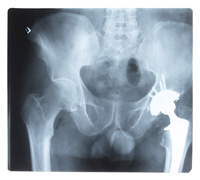

Are Osteoporosis Drugs Making Your Bones Weaker?

Perhaps the most devastating side effect was that long-term use by women who did NOT have osteoporosis might lead to weaker bones!

The way bisphosphonates work is by slowing cells that break down bone. (Those cells are called osteoclasts.) The problem is that by interrupting the body's normal cycle of tearing down and repair, the small stress fractures our body endures may not be able to heal properly.

Tests show that these drugs do help build bone the first five years, but for periods longer than that, bones may actually become more brittle. In May of 2011, Swedish researchers reviewed data on approximately 1.52 million women. They found that women who took bisphosphonates the longest had the highest risk of thigh fractures.